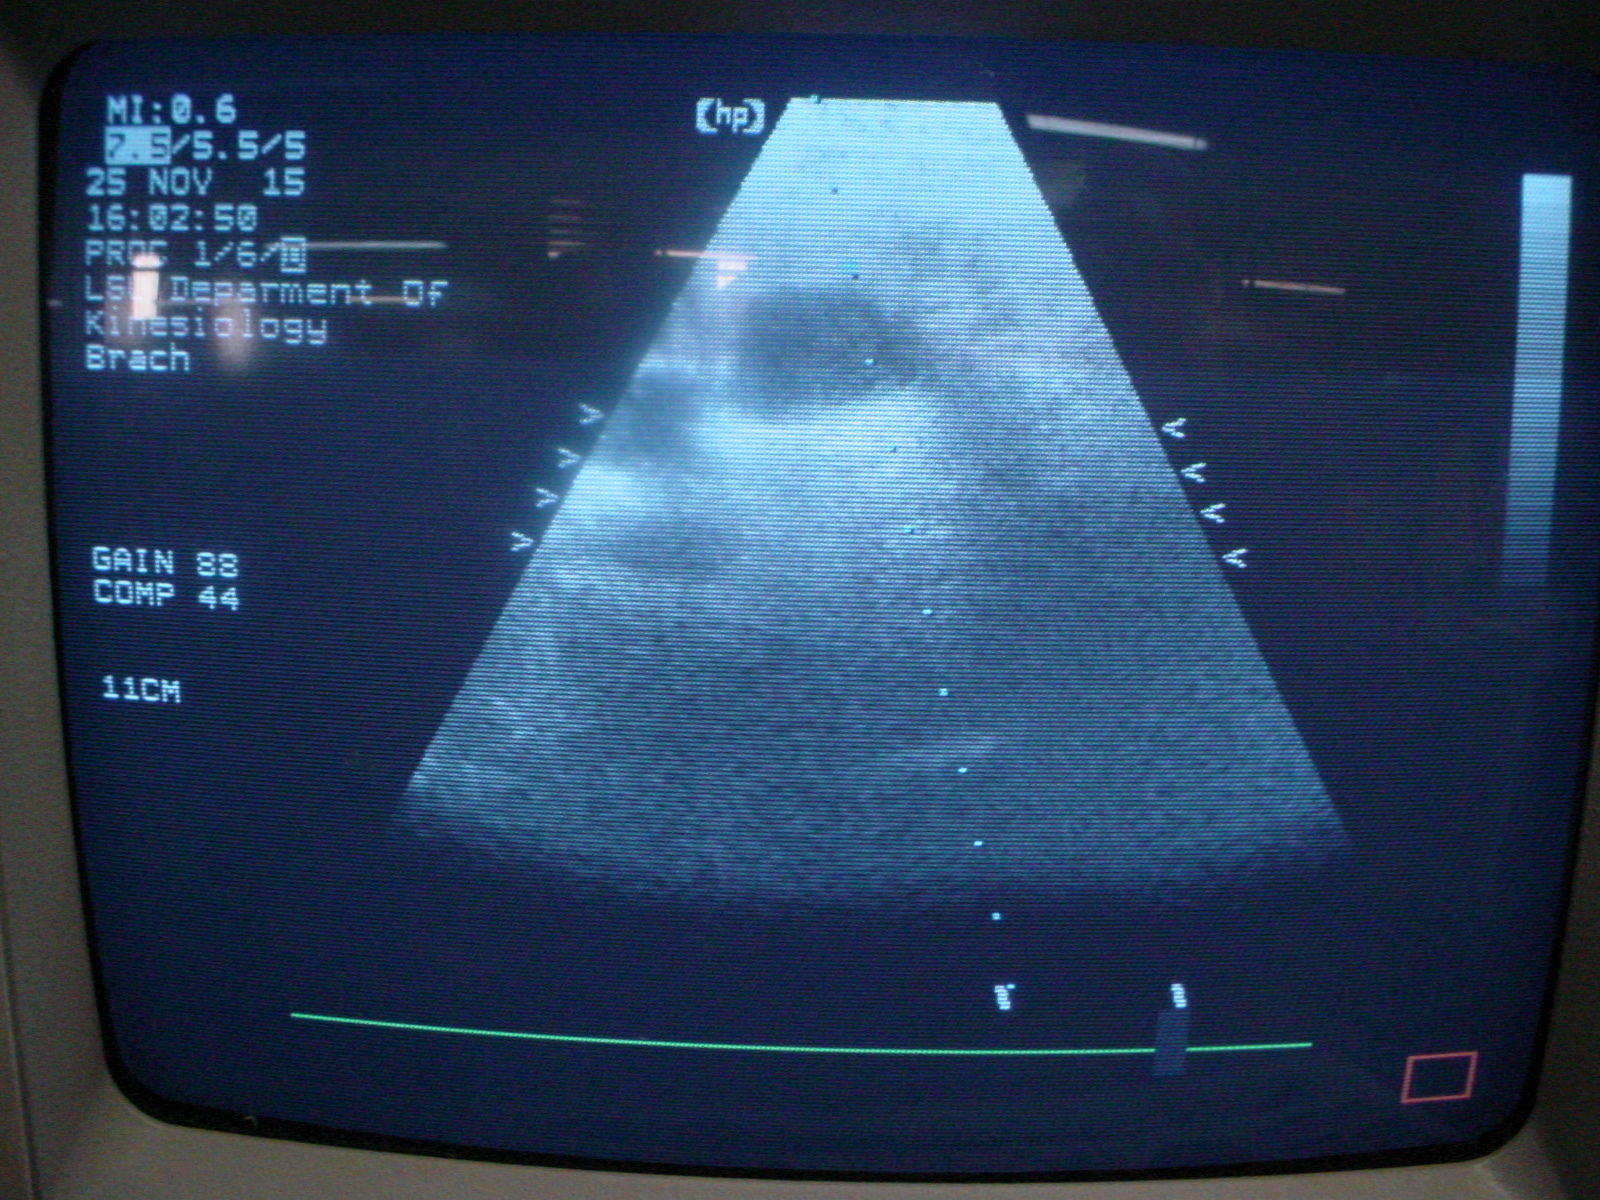

The Agilent HP M2406A Sonos 2000 Cardio Ultrasound is designed to provide unmatched image clarity. It uses advanced imaging technology that enhances visualization of cardiac structures and functions. Because of its high-frequency Philips 212588 probe operating at 7.5/5 MHz, the ultrasound delivers superior resolution. This means doctors can make more accurate diagnoses, and patients receive better care.